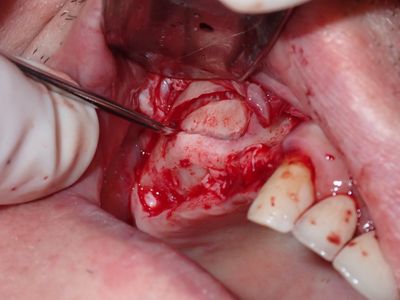

JGolos - R Sinus Augmentation

Very limited bone. window prepared with rotary and piezo electric instrumentation. no evidence of sinus membrane perforation, 1st layer: collatape 2nd layer: 80/20 mix of mineralized cortical/xenograft, membrane placed in internal aspect of window, additional bone on buccal followed by membrane. Tension-free primary closure.